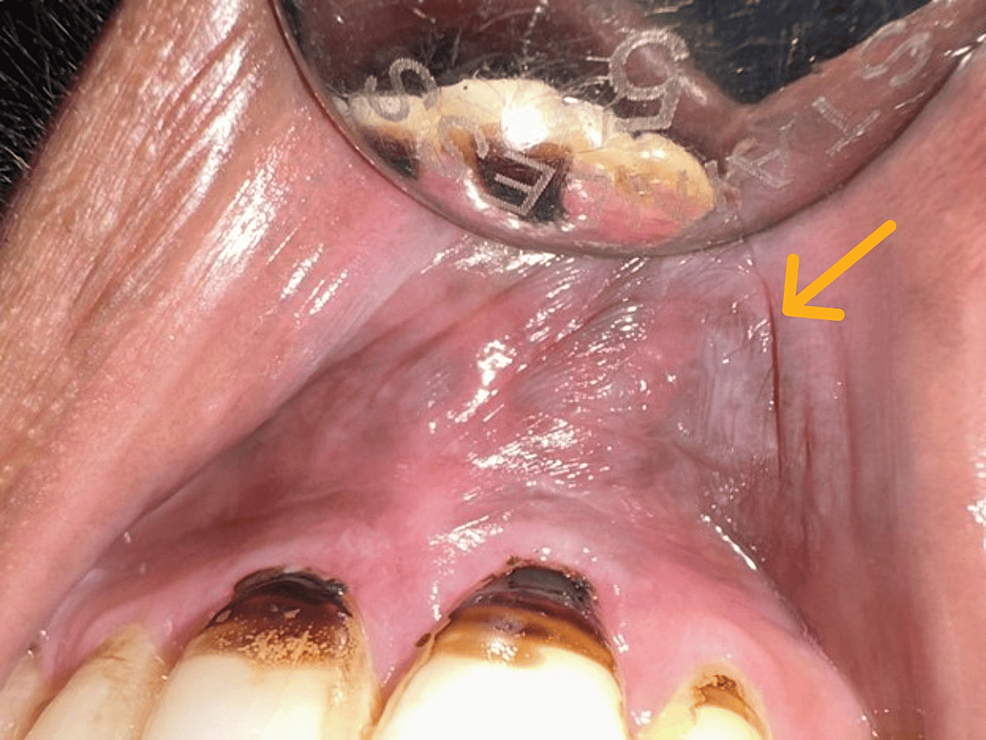

The characteristic appearance is a gray/white mucosal discoloration with a wrinkled or fissured surface texture. there is a strong association between tobacco use and the development of mucosal white patches such as tobacco. smokeless tobacco keratosis presents as a characteristic white corrugated plaque on the oral mucosa where the tobacco is placed. the histologic features of frictional keratosis from the tongue, lip or buccal mucosa vary slightly depending on. Smokeless tobacco keratosis is a reversible alteration of the oral mucosa in immediate contact with a smokeless tobacco product (chewing tobacco, moist snuff, dry snuff). this paper presents features of tobacco pouch keratosis and aims to highlight the oral effects of smokeless tobacco, management, and.

Lower labial sulcus of a patient showing tobacco pouch keratosis in... Download Scientific Diagram Tobacco Pouch Keratosis Biopsy this paper presents features of tobacco pouch keratosis and aims to highlight the oral effects of smokeless tobacco, management, and. smokeless tobacco keratosis presents as a characteristic white corrugated plaque on the oral mucosa where the tobacco is placed. Smokeless tobacco keratosis is a reversible alteration of the oral mucosa in immediate contact with a smokeless tobacco product. Tobacco Pouch Keratosis Biopsy.